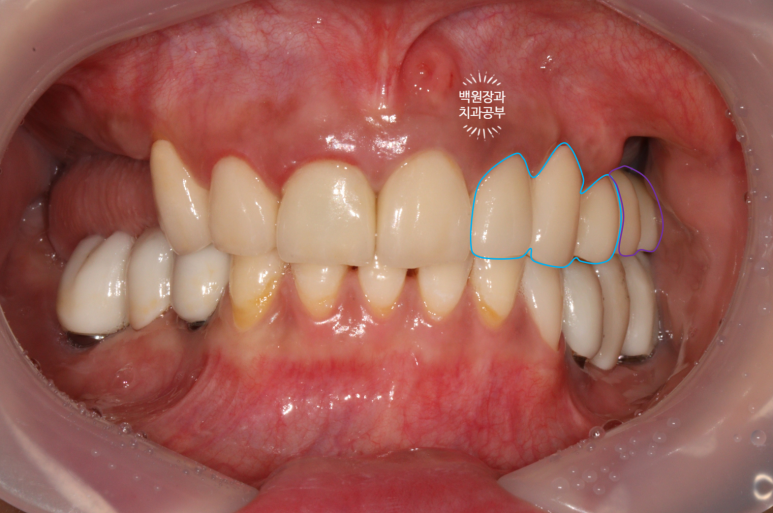

앞니 지르코니아 브릿지와 왼쪽 어금니 임플란트 완성!

앞니 지르코니아 브릿지와 왼쪽 어금니 임플란트가 완성되었습니다.

너무 색깔도 깔끔하게 잘 나오고... 만족스러운데요, 어디가 무엇인지 아시겠어요?

파란색으로 표시된 3개짜리가 앞니 지르코니아 브릿지이고,

보라색으로 표시된 2개짜리가 어금니 임플란트입니다.

진짜.. 내 치아라고 해도 잘 모르실거에요.

오래전에 하셨다는 아래 어금니 임플란트는 벌써 잇몸이 내려가 은색이 비쳐보이고 있네요... 여튼 이번에 새로한 치아들이 더 이쁘다는 말씀!